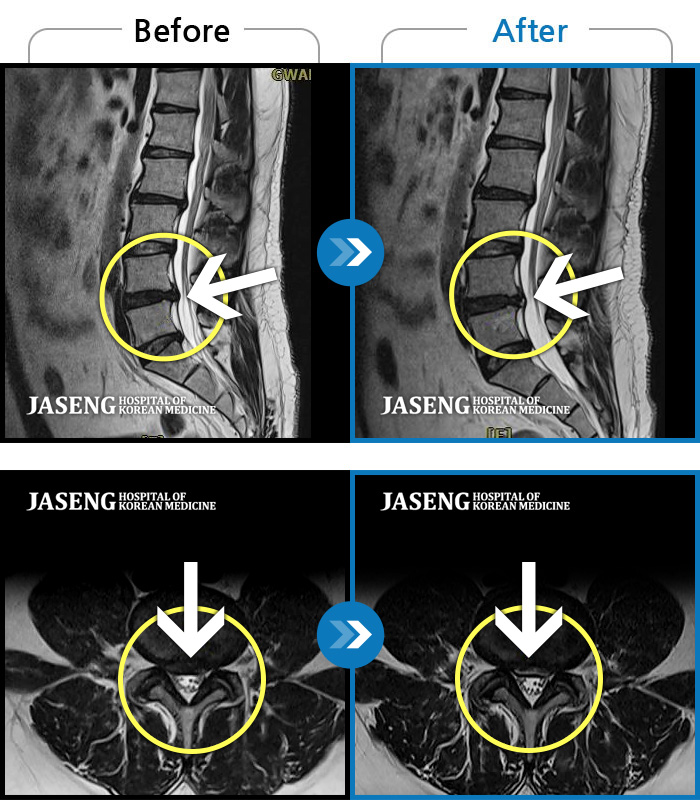

Before

After

허리 통증과 우측 허벅지 통증 및 저림 증상 지속되어 내원하셨습니다.

2022.08.20 ~ 2024.11.08